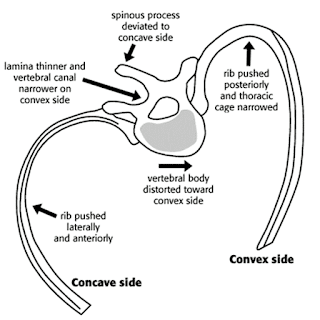

3-dimensional problem, with the spine rotating around itself as it bends to the

side. The way to visualize this is to

imagine a water slide, as it turns to the side, it also rotates…just like the

spine in scoliosis and how the spine twists the ribs around.